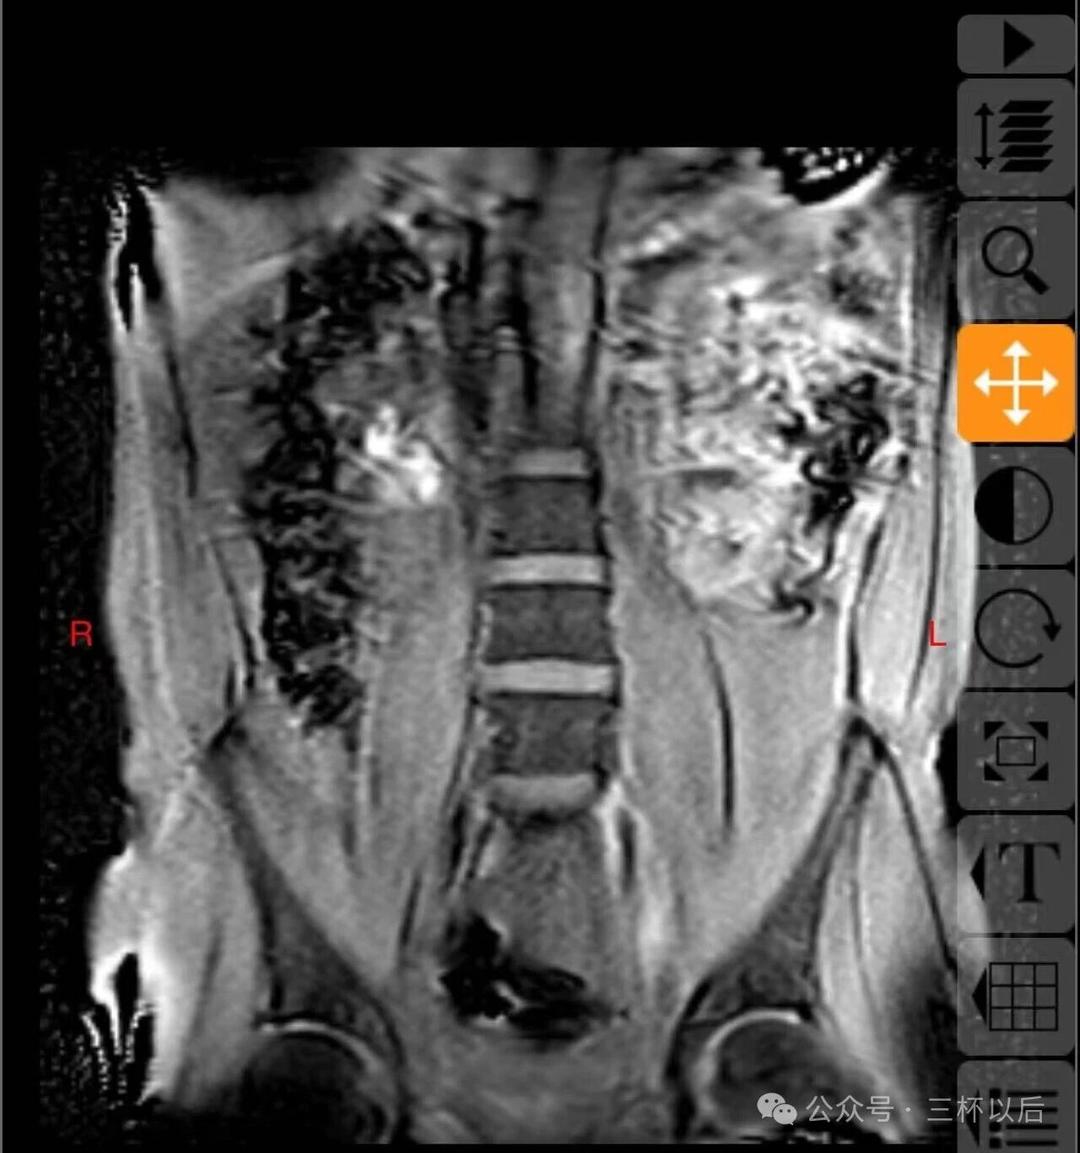

顺便贴一下拍的片子,如果有懂行的欢迎给我建议,我听劝的。真真希望能恢复如初,现在每天都能感受到疼痛,用了各种办法也不管用。